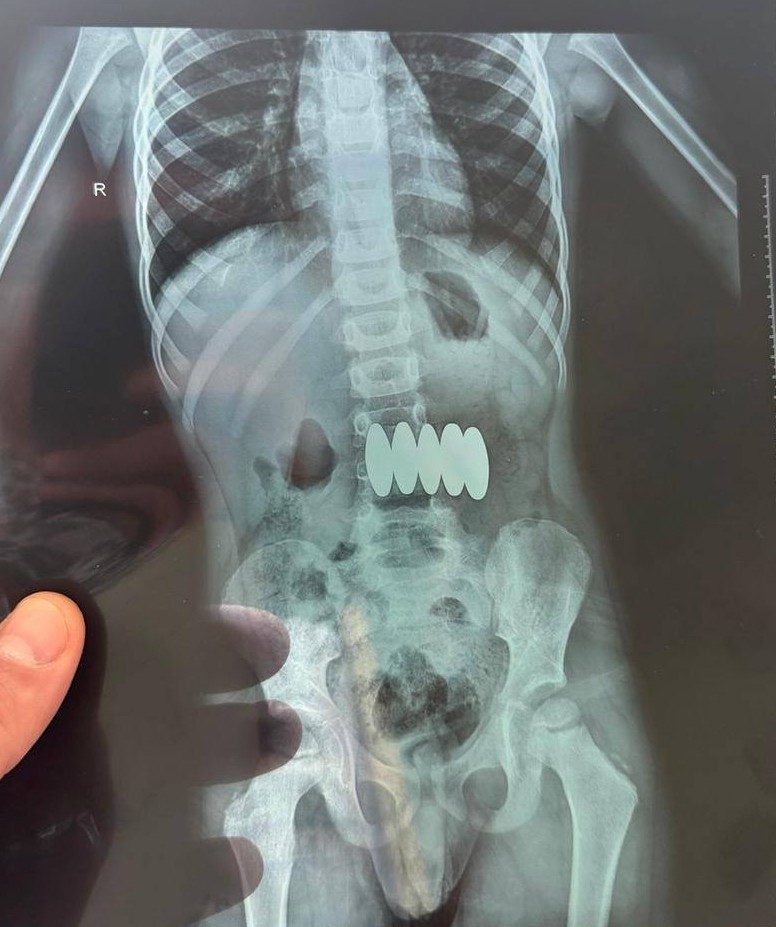

Як йдеться у дописі, пацієнта доставили до лікарні з ознаками кишкової непрохідності. Потім виявили, що хлопчик проковтнув п’ять магнітів.

Дитині провели ендоскопічне втручання і вилучили чотири магніти. Ще один вийшов самостійно.